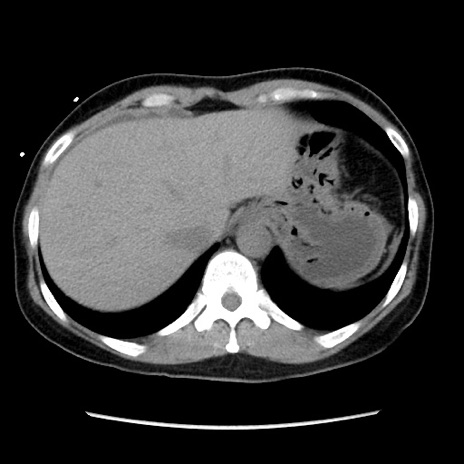

症例10(横断像)

【症例】 50歳代女性

【主訴】 腹痛

【現病歴】前日生レバーを食べた。今朝に排便あり。 昼前に突然発症の腹痛を生じ、当院救急外来を受診した。

【既往歴】 子宮筋腫にてで子宮全摘後

【身体所見】 意識清明、腹部:平坦、軟、下腹部やや左を中心に圧痛・反跳痛あり、筋性防御あり

【データ】WBC 7800、CRP 0.07